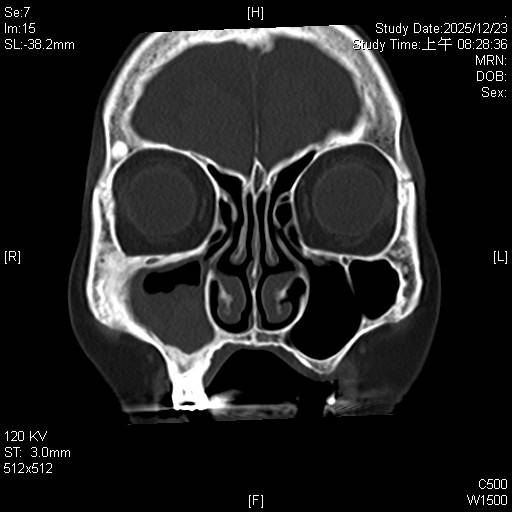

東元綜合醫院耳鼻喉科詹健暘主治醫師表示,阿嬤經過診斷為「慢性鼻竇炎,伴隨黴菌性鼻竇炎(fungal sinusitis)」。這類疾病在台灣潮濕的氣候環境下相當常見,黴菌塊(或稱黴菌球)常堆積在單側上頜竇,屬於非侵襲性黴菌感染,但在鼻竇內會不斷堆積成團塊,典型的表現為單側或局部鼻竇阻塞、鼻涕倒流,甚至頭痛。

考量高齡病人,手術治療面臨最大的挑戰在於「麻醉風險」。90歲長輩通常伴隨心血管或肺部功能退化,全身麻醉後的甦醒及併發症風險較高。所以經詳細評估後,決定採取局部麻醉下的「鼻竇內視鏡微創手術(functional endoscopic sinus surgery, FESS)」來治療。